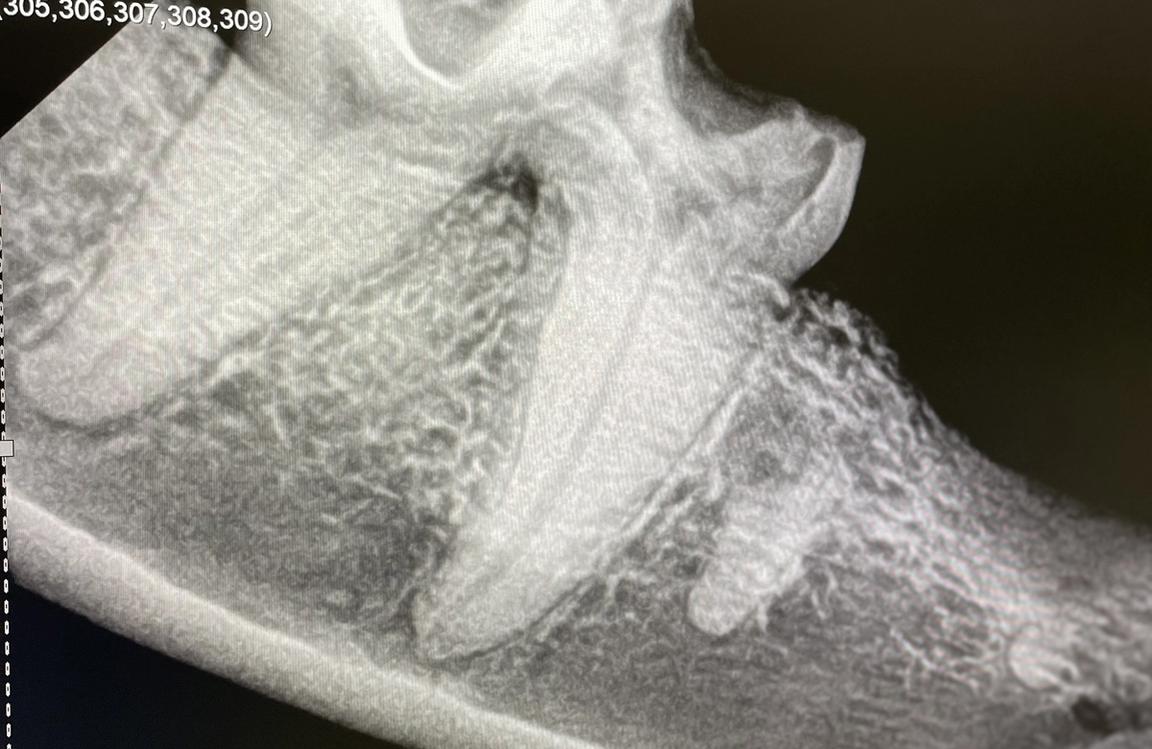

Ohne Zahnröntgen kann nur der sichtbare Teil des Zahnes und der Maulhöhle beurteilt werden. Sie sind unumgänglich, um „versteckte“ Probleme zu entdecken, wie z.B. Frakturen oder Abszesse der Zahnwurzeln, resorptive Läsionen (FORL) der Zähne bei der Katze, Entzündungen der Pulpahöhle (das ist das Innere des Zahnes) oder Veränderungen des Kieferknochens. Mit Hilfe des Zahnröntgens können auch von Geburt an bestehende Probleme wie Zahnzysten, Zahnfehlstellungen oder fehlende Zahnanlagen entdeckt werden.

Falls eine Zahnsanierung oder Behandlungen nicht auf einmal, sondern in zwei oder mehr Stadien durchgeführt werden, helfen Zahnröntgen auch bei der genauen Planung der weiteren Schritte. Außerdem kann damit ein Fortschreiten von Erkrankungen der Zähne oder des Kiefers überwacht werden. Und ganz wichtig: nach einer Zahnextraktion kann mit dem Zahnröntgen überprüft werden, ob auch alle Wurzelreste entfernt wurden.

Die Bilder werden intraoral erstellt, das heißt eine dünne und flexible Speicherfolie für die digitalen Bilder befindet sich für die Aufnahmen in der Maulhöhle des Tieres. Auf diese Weise ist die Qualität der Bilder am hochwertigsten. Um alle Zähne der Maulhöhle darzustellen sind im Normalfall zwischen 6 und 10 Aufnahmen nötig, die Bilder selber werden dann digital auf einem Bildschirm dargestellt. Die Strahlenbelastung ist beim intraoralen digitalen Röntgen übrigens extrem gering und stellt daher keine nennenswerte Gesundheitsbelastung für unsere Patienten dar.